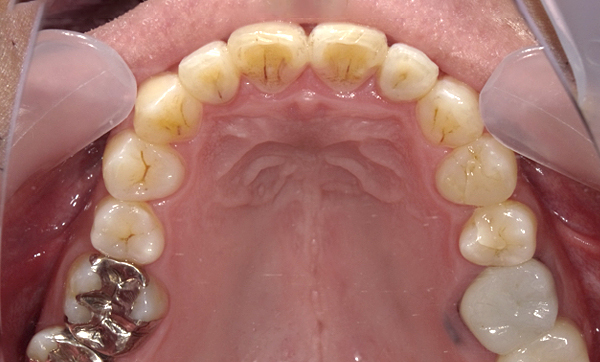

症例_001 前歯「八の字/V字型」症例

治療期間:17ヶ月金額:54万円+税20代女性八の字/V字型

| Before | After |